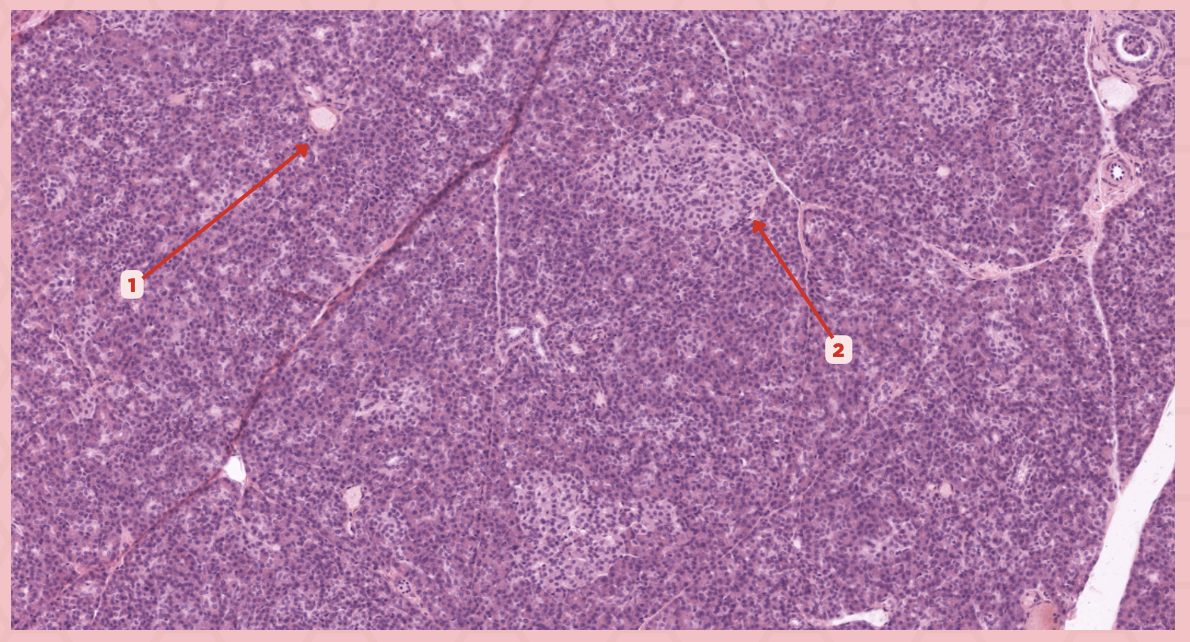

Pancreas

Identify the specimen.

Islets of Langerhans

Identify the structure labeled as 1.

Pancreatic Acini

Identify the structure labeled as 2.

Reticular Tissue

Identify the structure labeled as 3.

Beta-cells

Which cells occupy the central area of #1?

Pancreatic Acini

#3 delineates the pale- staining cells from the darker-staining cells. What do you call the darker-staining cells?